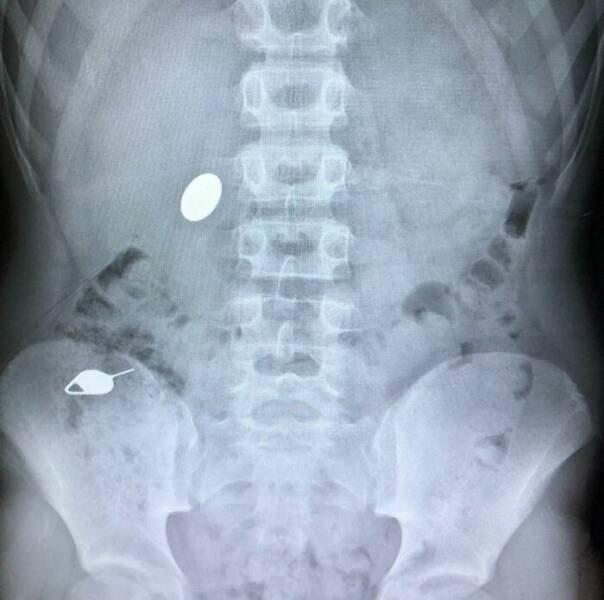

13. «Мой ребёнок проглотил монету, показывая своему младшему брату, как он случайно проглотил Sim-ключ накануне»